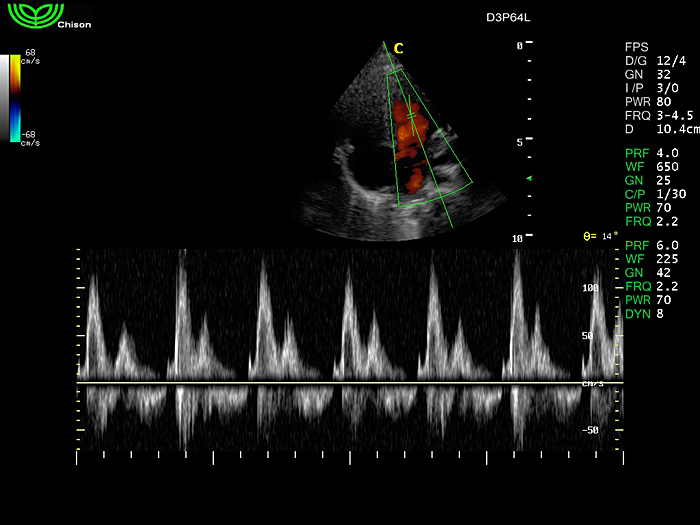

D3P64L 3.0МГц, фазированная решетка.

2.0МГц – 4.4МГц. Применения: кардиология, брюшная полость, акушерство. |